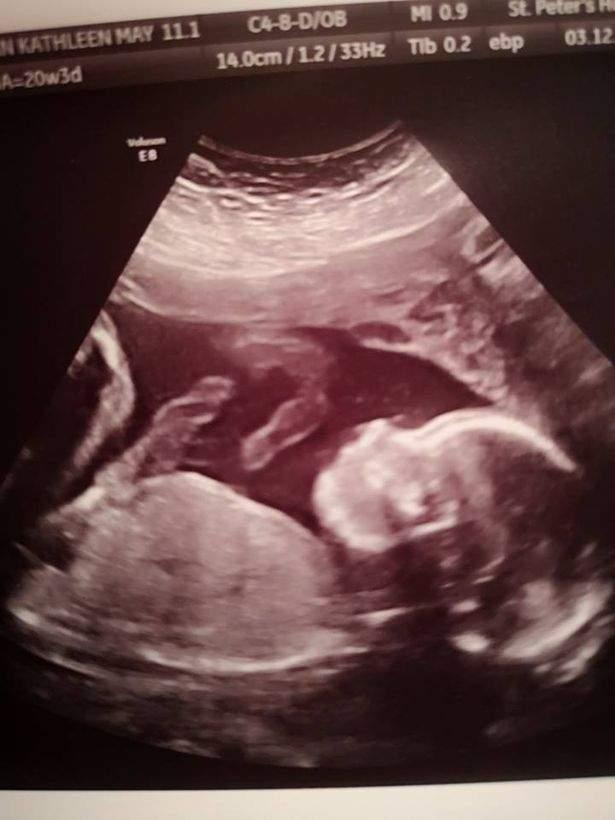

Potrivit The Mirror, în cea de-a 20-a săptămână de sarcină, medicii au descoperit că bebelușul are splina bifidă, cu defect de închidere de os la coloana vertebrală, ceea ce i-ar fi provocat mari probleme de locomoție, după naștere.

Patru săptămâni mai târziu, medicii britanici, ajutați de cei belgieni au intrat în sala de operații cu tânăra însărcinată de 26 de ani. Printr-o procedură revoluționară, copilul a fost scos din pântece, tratat, iar apoi pus la loc. Intervenţia chirurgicală a fost calificată drept o mare reuşită, iar starea de sănătate a copilului este foarte bună.